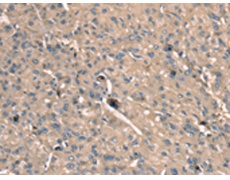

IHC positive control: |

Human liver cancer and Human esophagus cancer |

IHC Recommend dilution: |

25-100 |